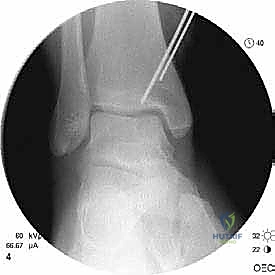

- التصوير بالأشعة السينية (X-rays): الخطوة الأولى لاستبعاد الكسور الكبيرة وتقييم المحاذاة العامة للعظام. قد تظهر الأشعة السينية الآفات الكبيرة، لكنها غالباً ما تفشل في إظهار التلف الغضروفي المبكر.

- التصوير المقطعي المحوسب (CT Scan): ضروري جداً للآفات الكبيرة. يوفر الـ CT صورة ثلاثية الأبعاد للعظم، مما يساعد الجراح في التخطيط الدقيق لعملية قطع العظم وحجم الطعم المطلوب زراعته.